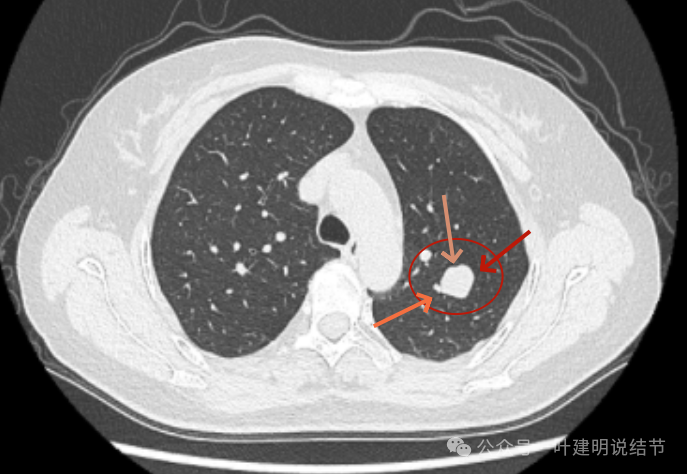

2024年10月,病灶较2019年时明显显得大了一些,挨着邻近血管了。

2023年12月,与血管已经贴着了。整体较最早时大了不少。

纵隔窗增强见血管与病灶没有间隙,病灶内部密度不均。

左上叶这个病灶看影像感觉边缘比较光滑,内部密度较为均匀,似乎是良性的。但我们如果将其2019年到2023年底的最大层面的影像放在一起对比,病灶是逐渐有增大的。2023年12月的肿块出现浅分叶、整体感觉鼓鼓的,原来病灶与旁边血管是有距离的,但最近这次的已经紧贴着了。但在纵隔窗看,病灶并无钙化或内部坏死密度,说明不太符合肉芽肿性炎或慢性炎性病灶。我觉得要十分倾向恶性肿瘤!低度恶性或交界性肿瘤可能性大。之前我碰到过随访10年的边缘光滑的实性病灶,从3厘米增大到8厘米多,术后是神经内分泌肿瘤的。我的想法还是要考虑切了,术前也可再复查下PET-CT,看看代谢是否活跃。但其实即使代谢轻度增高,也是放着不放心的。若是无代谢的,当然则与恶性不太符合(这种可能性是小的,无代谢不可能又增大)。这个位置穿刺可试试,但有点深,是否可行要与穿刺实施的科室医生沟通看看,若穿刺恶性仍得开刀,穿刺没见到癌细胞,但随访增大仍不放心。个人其实不是特别推荐穿刺。意见供参考!